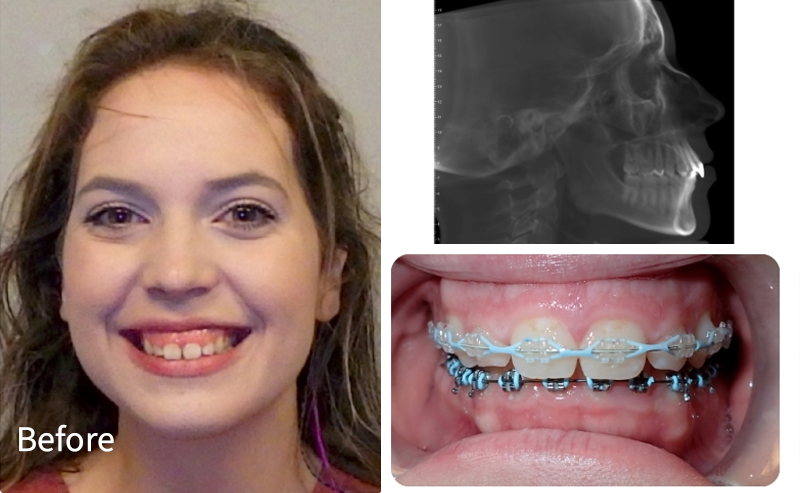

Crowding Corrected + Improved Bite

What we did

This patient had moderate crowding and bite imbalance. With braces, we aligned the teeth, created space where needed, and improved overall bite function for a healthier, more confident smile.